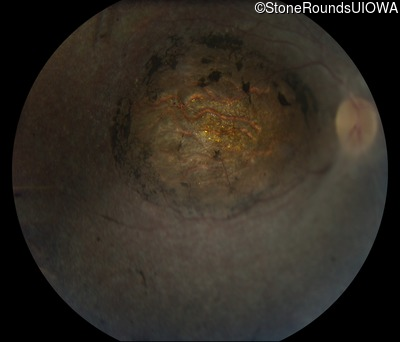

Age at visit: 18 years

This 18 year old woman was noted to have nystagmus shortly after birth. She has no recollection of any formed vision at any time in her life.

Diagnosis & molecular findings

Leber Congenital Amaurosis NMNAT1 Glu257Lys GAG>AAG Chr1:10034708-10042182del AR